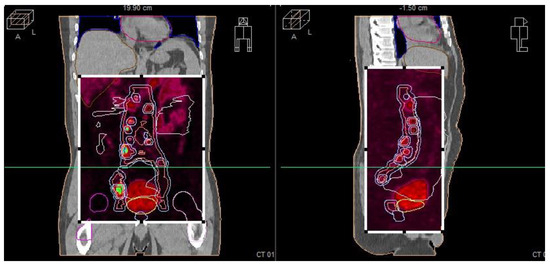

During the planning phase of the radiotherapy treatment course, a PET/CT scan was performed to delineate the metastatic sites accurately and guide radiotherapy planning. The radiotherapy regimen included teleradiotherapy targeting the prostate and affected lymph nodes with radical intent, utilizing a simultaneous integrated boost (SIB) approach with 45 Gy/60 Gy delivered in 25 fractions (Figure 2). Additionally, a high-dose–rate (HDR) brachytherapy boost of 15 Gy was administered in a single fraction to the prostate to achieve maximum local control (Figure 3).

Pre-radiotherapy PET-CT imaging (Figure 5) showed extensive lymph node metastases and high metabolic activity in the prostate. Following radiotherapy, the patient’s PSA level dropped below the edge of detection, indicating complete biochemical remission. This significant response was confirmed through follow-up imaging and clinical assessments.

Figure 5. Radiotherapy treatment planning—PET-CT—showing metastatic sites in the prostate and lymph nodes.